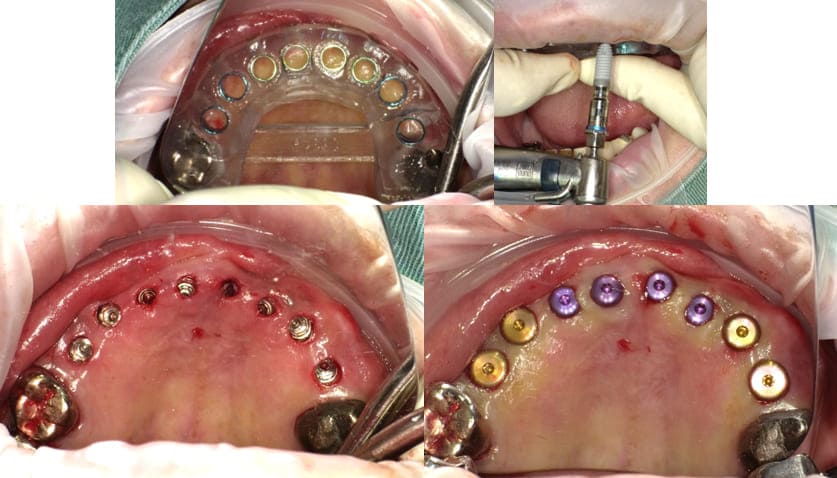

治療

上顎前歯部#12,23を抜歯予定でブリッジを除去したが#21が歯の破折により保存不可能と診断して#21も同日抜歯して仮歯を入れた。

他の温存不可能な残根も抜歯して上顎にインプラント5本を埋入した。なお#16に関してはソケットリフトを併用した。

-

- 治療時の画像(出血などの症例画像あり)

上顎のインプラント埋入後約1か月で、下顎臼歯部#35,36,44,45,46にインプラント埋入を行った。

上顎インプラント埋入手術後4ヶ月でインプラント体と骨の結合を確認して両側上下顎臼歯部のインプラントに上部構造(歯の部分)を装着した。

臼歯部のVertical Stopを確保した上で上顎前歯部のインプラント埋入手術を行った。

上顎前歯部インプラント埋入を行った後3ヶ月で前歯部のインプラントの歯の部分を装着するための印象、咬合採得と温存できた#13,12,21への歯冠補綴を行った(歯科技工士さん立ち会い)。